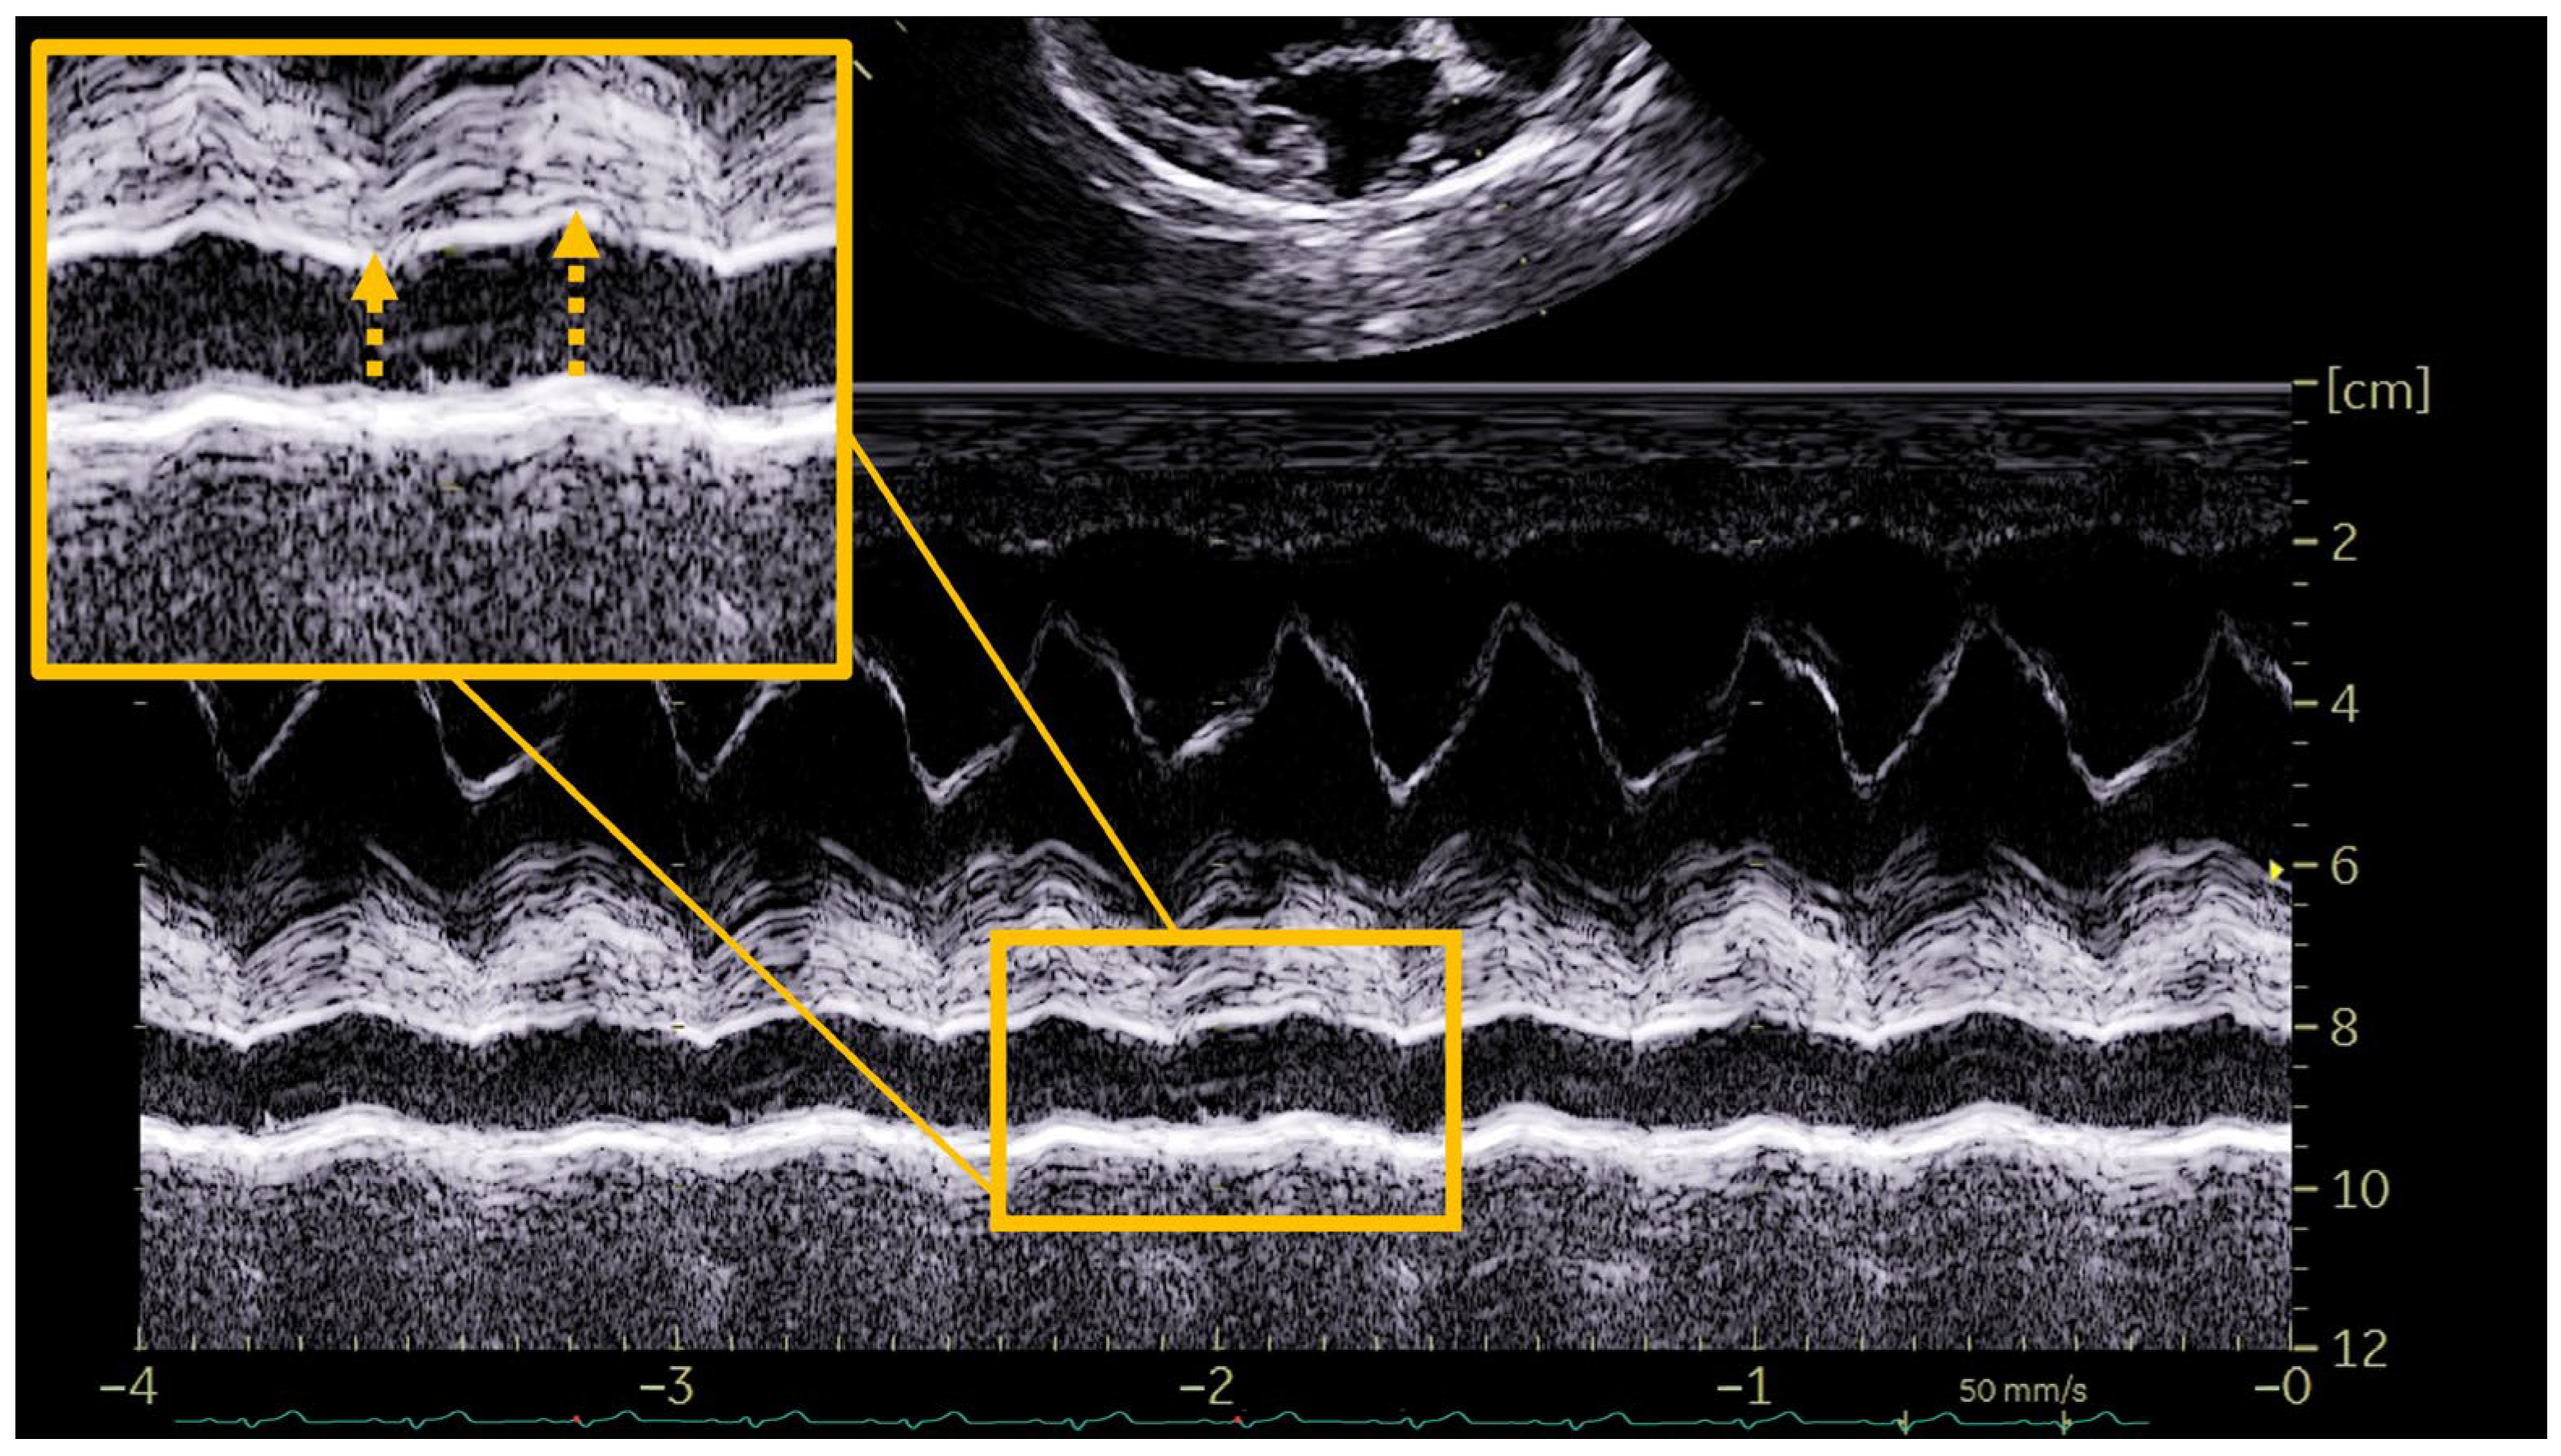

The determination of the presence of PH was based on the two different methods of obtaining the RPADi through the use of echocardiographic M-mode and 2D mode, being a value < 30% correlated in both cases with the presence of moderate or severe PH (>50 mmHg) [8,11]. To determine the RPADi using the Visser et al., method [11], the right parasternal short-axis view was applied at the level of the pulmonary trunk bifurcation, clearly observing the progression of the right and left branches. An adequate two-dimensional image with direct visualization of the longitudinal axis of the right pulmonary artery was obtained in all cases. The minimum diastolic and maximum systolic internal diameters were measured with the “trailing edge to leading edge” (te-le) method, using the same location of the right pulmonary artery (RPADVisser). Special care was taken to take measurements of the farthest portion, avoiding including the aorta (Ao) in the image (Figure 1). On the other hand, the determination of the RPADi using the Venco et al. method [8] was based on the right parasternal long-axis view of four cardiac chambers. M-mode was used in this case on the transverse axis of the right pulmonary artery when the left atrium, and pulmonary artery and vein were accurately observed. The right pulmonary artery diameters were measured using the “leading edge to leading edge” (le-le) measurement convention (RPADVenco) (Figure 2). In both cases, systolic diameter was measured at the maximum (T wave) and diastolic diameter at the smallest (Q wave) dimensions. The RPADi was calculated as the percentage difference in right pulmonary artery diameter in systole and diastole, using the following formula: RPADi = [(RPAmax − RPAmin)/RPAmax] × 100, as previously described [10].

Figure 2.

Representative image of the right pulmonary artery distensibility index (RPADi) measurement using the method of Venco et al. [6] in a dog infected by Dirofilaria immitis and with pulmonary hypertension. The right parasternal long-axis view of four cardiac chambers was optimized and M-mode was used on the transverse axis of the right pulmonary artery when the left atrium and pulmonary artery and vein were accurately observed. Systolic diameter was measured at the maximum dimension (T wave) and diastolic diameter at the smallest dimension (Q wave). The right pulmonary artery diameters were measured using the “leading edge to leading edge” measurement convention.